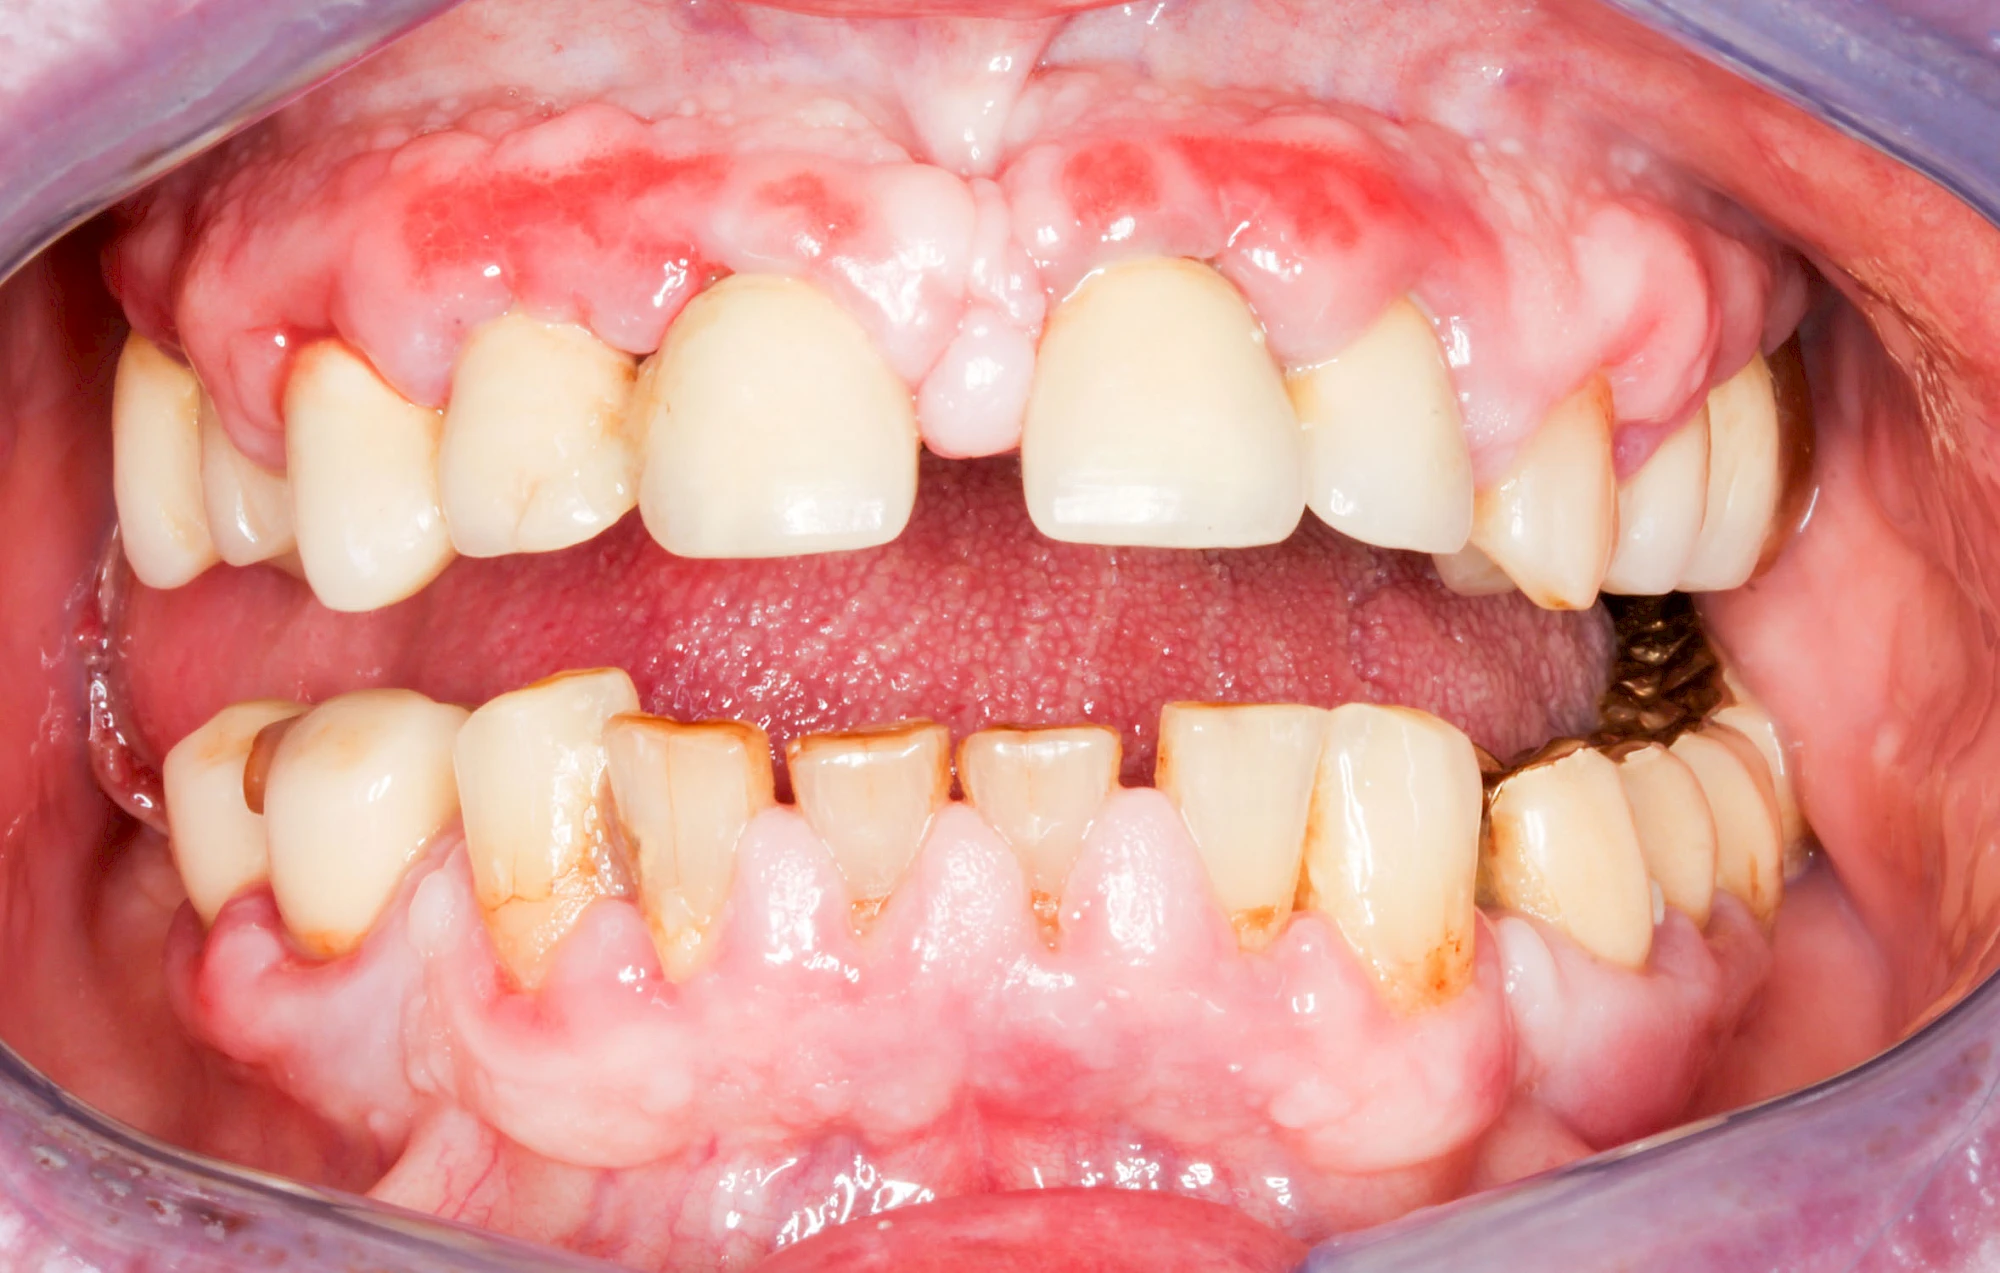

Bakterien in den Zahnbelägen greifen neben den Zähnen auch das Zahnfleisch (Gingiva) und den gesamten Zahnhalteapparat (Parodont) an. Der Körper reagiert mit einer Entzündung, sichtbar als Rötung und Schwellung. Meist blutet das Zahnfleisch z .B. beim Essen oder auch beim Putzen der Zähne.

Ist zunächst nur das Zahnfleisch von der Entzündung betroffen, spricht man von Gingivitis. Später, wenn auch der Knochen um die Zähne herum entzündet ist, spricht man von einer Parodontitis. Bei der Parodontitis wird der Knochen nach und nach abgebaut und das Zahnfleisch zieht sich zurück. Die Zahnhälse und Zahnwurzeloberflächen liegen mehr und mehr frei. Die Zähne werden zunehmend lockerer und fallen schließlich aus.

Bei Schwellung, Rötung oder Blutung des Zahnfleisches sollte neben der Intensivierung und Optimierung der Mundhyiene der Zahnarzt kontaktiert werden.